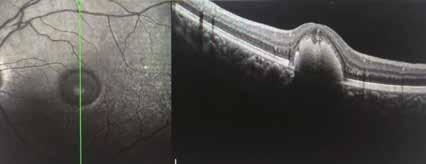

Nel corso del follow-up di tali pazienti si verificava spesso, come ben evidenziato dall’imaging in auto-fluorescenza (AF) nel tempo, un rapido e significativo incremento delle aree atrofiche, solo pochi mesi dopo la sostituzione del DHA algale dall’integratore Areds2 con olio di Krill, cosa mai avvenuta nel precedente lungo follow-up dei medesimi pazienti durante integrazione con DHA algale. (Fig. 2)

Fig. 1. Imaging infrarosso ed OCT mostra un Rapido ed insolito appianamento di ampio distacco dell’EPR maculare in DMS in donna di 75 aa, con significativo miglioramento visivo da 0.6 logmar a 0.1 logmar e nell’integrità delle linee recettoriale nella zona ellissoide, in particolare in assenza di aree atrofiche successive al riassorbimento.

Baseline: notare chiazze biancastre segno di sofferenza EPR

18 mos dopo formula areds2 & DHA Algale: chiazze tondeggianti scomparse

9 mos dopo rimozione DHA algale dalla formula Areds2

Fig. 2. Notare che nei 18 mesi di integrazione l’auto-fluorescenza della macula della paziente di 78 aa con AMD rimane libera da significative aree atrofiche, fintanto che il paziente continua ad assumere la formula antiox AREDS2 arricchita di olio algale, mentre solo 9 mesi dopo la sostituzione del DHA algale con DHA da pesce Krill, si osserva la rapida comparsa di significative ed invalidanti aree atrofiche a coinvolgere diffusamente l‘area maculare,altamente impattanti sull’acuità visiva della paziente fino a rendere estremamente difficoltosa la capacità di lettura, con un calo visivo fino a 2/10 da 8-9/10.